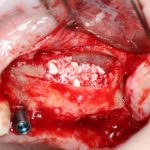

Глянем на то, что получилось:

Осталось адаптировать костный блок (убрать острые края), проверить его фиксацию и, при необходимости, добавить винты. Десятисекундное дело.